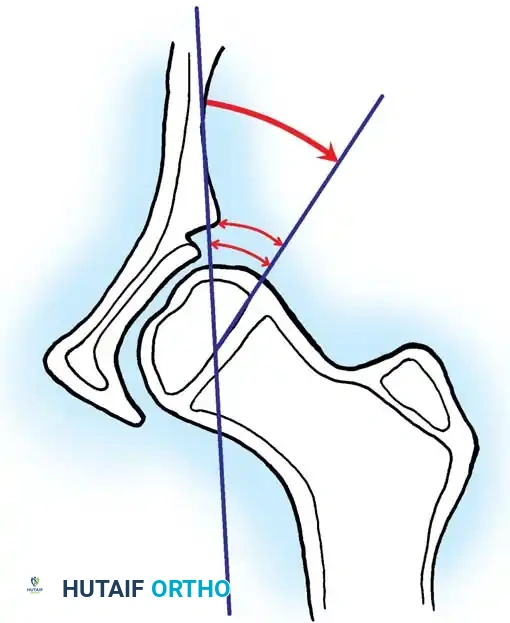

- Salter Innominate Osteotomy:

- Indications: Children aged 18 months to 6 years with a congruous joint but anterolateral acetabular deficiency.

- Biomechanics: A complete transverse cut is made through the ilium just above the acetabulum to the sciatic notch. The entire acetabulum is rotated anteriorly and laterally, hinging on the pubic symphysis.

- Fixation: A triangular bone graft (harvested from the iliac crest) is placed in the osteotomy site, and the construct is stabilized with threaded Kirschner wires.

Diagrammatic representation of the Salter Innominate Osteotomy. Note the complete iliac cut and the placement of the triangular bone graft to redirect the acetabulum.